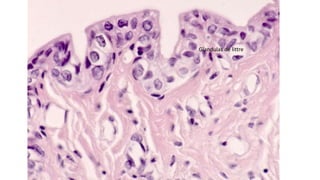

O documento descreve estruturas renais como a macula densa, células de Lacis e glândulas de Littre que fazem parte do aparelho yuxtaglomerular, responsável pela regulação da pressão arterial e do volume de fluidos no corpo.